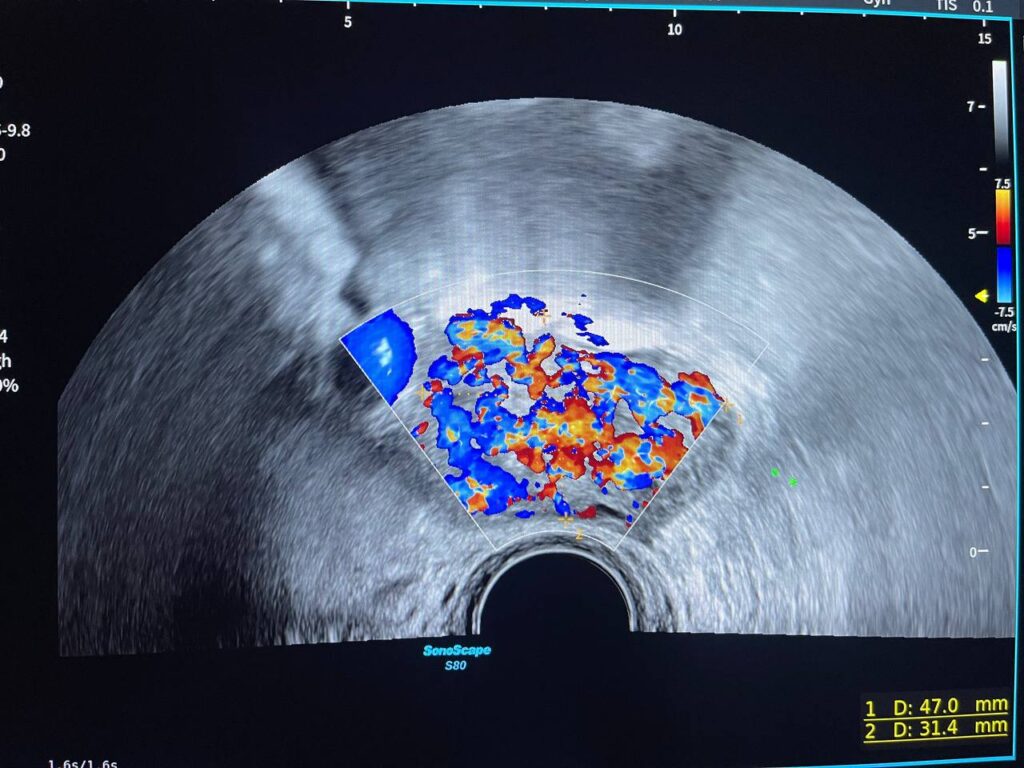

Presence of hyper vascular mass 47x31mm in the right cornua & within the interstitial layer , picture mostly of ectopic H Mole pregnancy , please for further study

Presence of hyper vascular mass 47x31mm in the right cornua & within the interstitial layer , picture mostly of ectopic H Mole pregnancy , please for further study